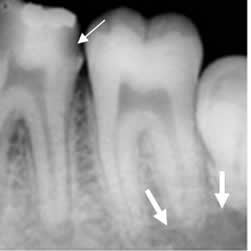

Fig 37. Enfermedad endodental.

Rx periapical. Se identifica caries. (Flecha gruesa). Extensión periapical de la infección, con disminución de la densidad del hueso que rodea las raíces. (Flechas delgadas).